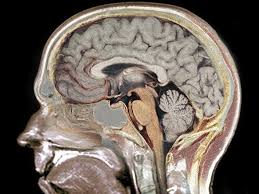

Os cientistas buscaram a explicação de como estas nanopartículas apareceram no cérebro, que é protegido de substâncias tóxicas por uma estrutura particular: a BHE (Barreira Hematoencefálica).

Equipes do CEA e da Universidade Joseph Fourier de Grenoble (sudeste da França) reconstituíram um modelo celular desta barreira protetora, associando células endoteliais (células da parede dos vasos sanguíneos), cultivadas em uma membrana semipermeável, e células gliais (do sistema nervoso).

Graças a este modelo, que contém as principais características da barreira hematoencefálica presente no homem, os cientistas mostraram que uma exposição in vitro aos nano-TiO2 provoca seu acúmulo nas células endoteliais. Isto implica também a ruptura da barreira de proteção, associada a uma inflamação.